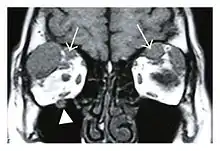

The extent of inflammation that can occur in IgG4-ROD is well demonstrated on magnetic resonance imaging (MRI).

![]() Swelling of the left superior and lateral rectus muscles, a mass lesion around the left optic disc (arrow), and enlargements of the left supraorbital nerve and the right infraorbital nerve (arrow heads) in a 60-year-old man with a serum IgG4 of 463 mg/dL.[1] (T1-weighted MRI) |